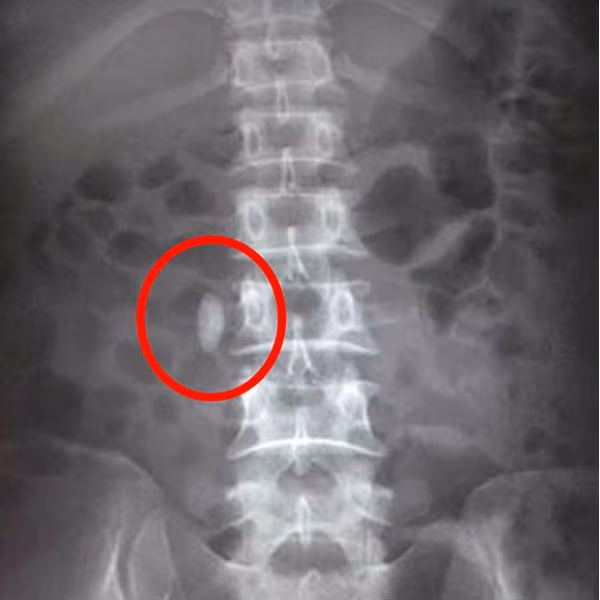

Việc chẩn đoán chủ yếu dựa vào X quang nhưng cũng có nhiều khó khăn vì thường là sỏi nhỏ, cản quang kém, dễ bị che khuất bởi các xương trên đường đi của niệu quản. Mặt khác ở vùng chậu còn rất nhiều loại hình cản quang không phải sỏi nên hình ảnh sỏi niệu quản rất khó để nhận biết.

Khi chụp X quang thận thường, sỏi niệu quản có 2 tính chất cơ bản:

– Hình ảnh sỏi niệu quản kéo dài một chiều; hay gặp là hình bầu dục, hình gậy, hình trám, hình tam giác, còn hình tròn thì hiếm gặp.

– Vị trí tương ứng với đường của niệu quản và hướng của nó tuỳ thuộc vào hướng của đoạn niệu quản chứa nó.

- Hình ảnh sỏi niệu quản khi chụp x quang thận thường.

Các tính chất khác (rất thay đổi):

– Số lượng: thông thường là một, đôi khi hình ảnh sỏi niệu quản nhìn thấy là dãy nhiều viên xếp dọc theo đường đi của niệu quản.

– Kích thước: rất thay đổi từ 1mm đến vài cm.

– Cấu trúc và bờ: Mặt nhẵn hoặc gồ ghề, đồng nhất hoặc xếp thành lớp.